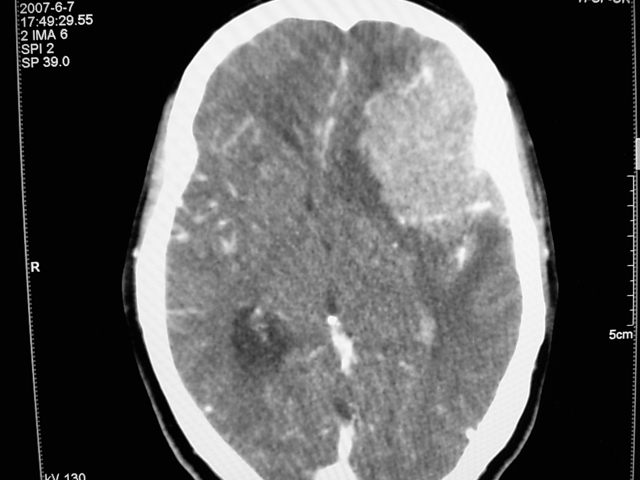

患者 女 63岁,近几周感觉头部不适来查体。

请调骨窗。多考虑前中颅窝脑外肿瘤,脑膜瘤、淋巴瘤或血管外皮瘤均有可能,蝶嵴脑膜瘤可能性最大。

左侧额颞部巨大肿块,平扫呈略高密度,增强明显强化,周围水肿明显,左侧侧脑室受压,右侧侧脑室扩大,中线明显右移,局部骨质增厚,支持脑膜瘤、大脑廉下疝。